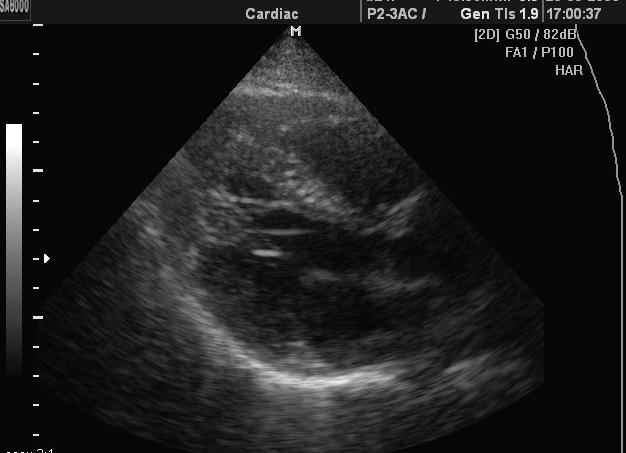

Дополнительную трабекулу преимущественно находят у новорожденных при плановом обследовании, или случайно, в более зрелом возрасте. Если возникла характерная для нее симптоматика, то выявлением патологии должен заняться кардиолог. Он проведет осмотр и опрос пациента. Собрав всю необходимую информацию, доктор назначит инструментальные методы обследования для определения причинного фактора. Их перечень можно увидеть ниже:

• Ультразвуковое исследование (УЗИ) сердечной мышцы позволяет оценить ее ритм и частоту сокращений. Оно абсолютно безопасно и помогает точно определить причину возникшего дискомфорта. Назначается подобное обследование в основном людям, у которых проблемы с дыханием, боли в области грудной клетки или изменение ее формы.

• Эхокардиография или ультразвуковое исследование сердца — эффективный способ обследования, помогает увидеть состояние сердечной мышцы, частоту ее сокращения и расслабления. А также показывает сердечный ритм, назначается людям, которые страдают затрудненным дыханием, болевыми ощущениями и покалываниями в области сердца, кроме того, в случае изменения формы грудной клетки. Данная процедура вовсе безопасна и позволяет установить причину всех проявляющихся симптомов.

2. Эхокардиография – относится к самым информативным манипуляциям, позволяющим определить все отклонения в функциональности сердечной мышцы. Методика с точностью определяет наличие трабекулы в органе.